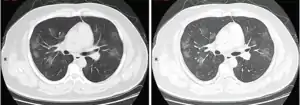

КТ грудної клітки іноді може допомогти визначити і охарактеризувати патологію легенів і дати неспецифічні результати при інфекції COVID-19. Систематичний огляд результатів комп'ютерної томографії грудної клітки у 919 пацієнтів описав типове ранній прояв COVID-19 як «двостороннє мультилобарне помутніння матового скла (GGO) з периферичним або заднім розподілом».[21] Одне дослідження показало, що чутливість КТ до інфекції COVID-19 склала 98 % порівняно з чутливістю ОТ-ПЛР (RT-PCR) на 71 %; проте це було зроблено в китайській провінції Ухань і не підлягає узагальненню.[22] Найбільш поширеними результатами комп'ютерної томографії були двостороннє загасання матового скла (плямисте або розсіяне) з субплевральним домінуванням, божевільним укладанням та консолідацією на більш пізніх стадіях.[23] Ці дані є неспецифічними і виявляються також при інших типах пневмонії. Невелике дослідження показало, що китайські рентгенологи продемонстрували чутливість 72-94 % і 24-94 % в диференціюванні COVID-19 від інших типів вірусної пневмонії з використанням комп'ютерної томографії.[24] Жодне дослідження ще не підтвердило точність і дискримінаційну цінність комп'ютерних томографій, щоб відрізнити COVID від інших вірусних пневмоній. Тому CDC не рекомендує CT для первинного скринінгу, як підкреслювалося в дзвінку COCA у четвер, 5 березня. Люди з підозрою на COVID повинні проходити RT-PCR, яка є найбільш специфічним тестом.

Типові результати комп'ютерної томографії

Комп'ютерна томографія стадії швидкого прогресування